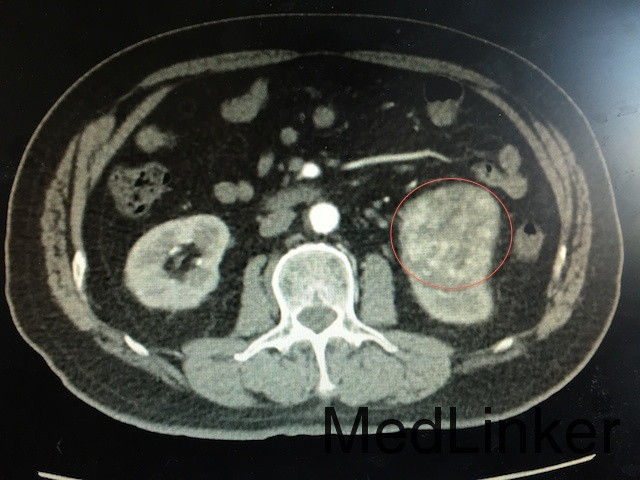

查体:左肾区叩痛可疑阳性 辅助检查:泌尿系CT平扫+强化如下图所示:左肾下极可见软组织密度团块影,突出肾轮廓并累及肾窦,大小约为6.6*6.1*5.7cm,动脉期呈不均匀强化,可见左肾动脉分支血供。

诊断:肾占位(肾恶习肿瘤可能性大) 治疗:肾癌根治术

随访:肾及肾周包膜切除,病理回报为肾透明细胞癌 讨论:肾恶性肿瘤主要与肾错构瘤鉴别,后者B超可见脂肪密度高回声,CT平扫为脂肪密度,CT增强强化比肾恶性肿瘤更明显。